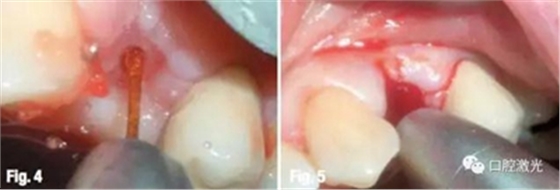

通過測(cè)量,種植的安全深度為12mm。選擇波長(zhǎng)為2780nm水激光(Er,Cr:YSGG),在浸潤(rùn)局部麻醉后,利用Z4/14激光工作尖在24中心處進(jìn)行切割氣化。激光設(shè)置為功率3W、脈沖能量150mJ、50%水、50%氣。激光發(fā)射方向由臨近牙齒和骨的形態(tài)決定。